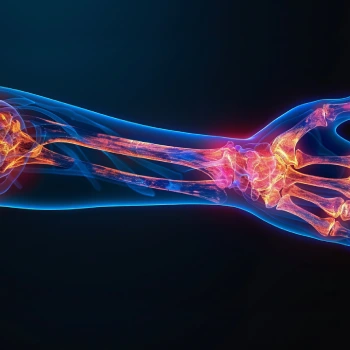

در این روش تصویر برداری یک صفحه (گیرنده یا دتکتور) در زیر عضو و قسمت مورد نظر قرار داده می شود و اشعه ایکس(دُز از اشعه جهت تشخیص) به همان قسمت که روی صفحه قرار گرفته تابنده می شود و توسط صفحه اطلاعات دریافت می شوند و همین اطلاعات پس از پردازش های لازم در نهایت عکس رادیولوژی به ما ارائه می دهد. کاربردهای رادیولوژی در منزل دقیقاً همان کاربرد رادیولوژی در بیمارستان ها می باشد از جمله بررسی انواع شکستگی ها، دررفتگی مفاصل، آرتروز مفاصل، دیدن پروتز های داخل استخوان از نظر بررسی موقعیت پروتز، آب آوردگی ریه(اِدم وافیوژن) و عفونت ریه، شکستگی دنده ها، انساد و وجود هوا در شکم و… می باشند. رادیولوژی در منزل تمام این خدمات را ارائه می دهد.

تصاویری از رادیولوژی در منزل توسط گاما پرتو